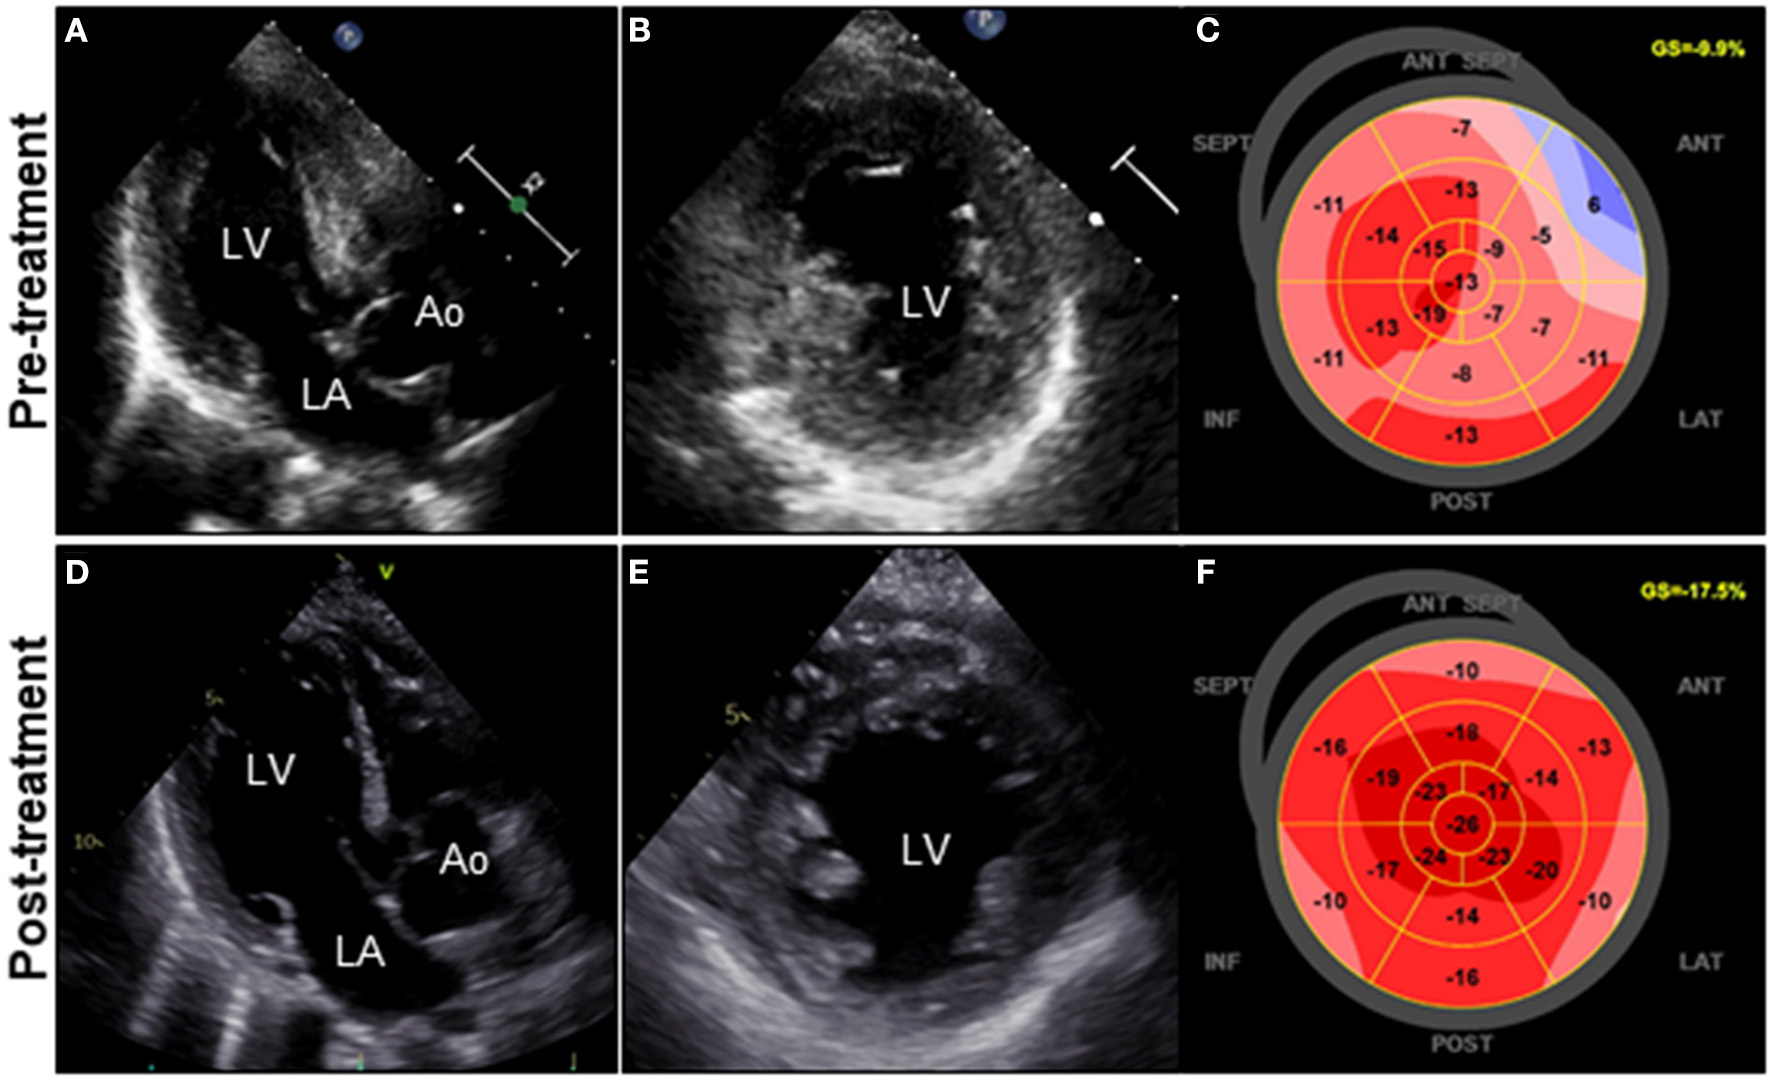

A 72-year-old woman was admitted to our hospital with worsening chest pain. She had a history of asthma and was treated with a fluticasone furoate/vilanterol (inhaler), theophylline (200 mg/day), ambroxol hydrochloride capsules (45 mg/day), montelukast (10 mg/day), and mequitazine (6 mg/day). Her treatment was aided with short-term use of oral prednisolone as required. The patient's general practitioner switched her from regular branded medications to generic medications 1 month prior to her admission. A week before admission, she experienced chest pain, characterized by chest tightness on exertion that disappeared on rest. Her symptoms worsened and were accompanied by dyspnea on effort (New York Heart Association class II–III). Her vital signs were as follows: blood pressure 118/73 mmHg, heart rate 87 beats/min, temperature 37.3°C, and oxygen saturation 97%. The physical and neurological examination results and chest radiographs were unremarkable. The electrocardiogram (ECG) showed pathologic Q waves in V2 to V3, and negative QRS complexes including rS morphology in the inferior leads, diagnosed as a left anterior fascicular block (Supplementary Figure 1A). The laboratory testing revealed a significant eosinophilia with an eosinophil percentage of 67.6% (normal <6%) and an absolute eosinophil count (AEC) of 10,410/μL (normal <500/μL), elevated brain natriuretic peptide level of 536 pg/mL (normal <18.4 pg/mL), and elevated cardiac biomarkers levels as follows: creatine kinase, 473 U/L (reference: 41–153 U/L); CK-MB, 39 U/L (normal <25 U/L); aspartate aminotransferase, 72 U/L (reference: 13–30 U/L); lactate dehydrogenase, 613 U/L (reference: 124–222 U/L); and high sensitivity cardiac troponin I, 47,875.3 pg/mL (normal <26.2 pg/mL). The levels of the inflammatory markers were also elevated—the C-reactive protein was 0.65 mg/dL (normal <0.3 mg/dL) and the erythrocyte sedimentation rate was >110 mm/h (reference: 3–15 mm/h). The results of renal function and urinalysis were normal. Further laboratory studies revealed elevated levels of serum IgE at 1,840 IU/mL (normal <173 IU/mL) and rheumatoid factor at 204 IU/mL (normal <15 IU/mL). In addition, the levels of the Th2 cytokines-related interleukins (IL) were also raised—IL-4 was 7.7 pg/mL (normal <3.9 pg/mL) and IL-5 was 30 pg/mL (normal <3.9 pg/mL). Anti-neutrophil cytoplasmic antibodies (ANCA) were not detected. Echocardiography revealed a mildly thickened myocardium and significant left ventricular (LV) systolic dysfunction with an ejection fraction of 43%. In addition, speckle-tracking echocardiography showed a reduced baseline global longitudinal strain of −9.9% (Figures 1A–C and Supplementary Video 1). Accordingly, we made a tentative diagnosis of acute coronary syndrome (ACS). An emergency coronary angiography was performed after pre-treatment with methylprednisolone (250 mg) that was administered to prevent allergic contrast reactions for the patient with asthma. The angiogram revealed normal epicardial coronary arteries. Therefore, acute EM was suspected, and cardiac magnetic resonance (CMR) was performed to assess the myocardial tissue (Figures 2A–C and Supplementary Video 2). Myocardial first-pass perfusion (FPP) imaging showed patchy and circumferential subendocardial perfusion defects (arrowheads), suggesting microvascular disorders. CMR also showed subendocardial late gadolinium enhancement (LGE) as multiple and lobulated high-signal intensity spots (arrows), which suggested vasculitis. The T2-weighted image showed a transmural high-intensity signal throughout the myocardium, corresponding to myocardial edema. Acute myocarditis was diagnosed based on the Lake–Louise criteria. These findings were consistent with acute EM. Simultaneously, an exhaustive diagnostic workup for hypereosinophilia was performed. Its differential diagnoses include hypersensitivity myocarditis (HSM), EGPA, parasitic infections, hematologic malignancies, and lymphocytic/idiopathic hypereosinophilic syndrome (HES). Considering the patient's recent medical history, HSM was initially suspected as the cause of EM. The generic drugs being administered to the patient were discontinued after admission. A subsequent endomyocardial biopsy (EMB) was performed, which demonstrated marked extravascular eosinophilic infiltrates without granulomatous and fibrinoid necrotizing vasculitis (Figure 3A). Numerous eosinophilic infiltrations, with degranulated eosinophils admixed with lymphocytes and myocyte necrosis, were observed in the myocardial interstitium that extended to the endocardium (Figures 3B,C). Moderate endocardial thickening and perivascular interstitial fibrosis were observed (data not shown). Immunostaining was performed to identify the major basic proteins revealed extensive staining in the endocardium and myocardial interstitium (Figure 3D). These findings led to the final diagnosis of acute EM. Subsequently, the patient was treated with intravenous methylprednisolone (1 g/day for 3 days), followed by oral prednisolone (1 mg/kg/day). The clinical response to steroid treatment was remarkable, with significant recovery of LV dysfunction, hypereosinophilia, and elevated cardiac enzyme levels within 21 days of steroid treatment (Figures 1D–F and Supplementary Video 3). Follow-up ECG showed resolution of all abnormal findings recognized during the initial ECG (Supplementary Figure 1B). On day 33, the patient was discharged after administration of prednisolone (15 mg/day), with a gradual tapering of the doses. On day 56, the patient remained asymptomatic, with fully recovered cardiac function observed on echocardiography (Supplementary Figure 2 and Supplementary Video 4). Moreover, the abnormal findings of the CMR resolved completely (Figures 2D–F and Supplementary Video 5). On day 75, prednisolone was tapered and finally discontinued in the outpatient clinic. However, her asthma precipitated again 2 weeks later, which was concurrent with an eosinophilia count of 1,512/μL. Since a thorough diagnostic workup for hypereosinophilia was negative, idiopathic HES was also considered. Although the patient had no clinical neurological manifestations, her CMR findings were suggestive of vasculitis, which encouraged us to perform a nerve conduction study that revealed mononeuritis multiplex. Eventually, as per the diagnostic criteria of the American College of Rheumatology (ACR) for EGPA, the patient met four of the six items (asthma, eosinophilia >10%, mononeuritis multiplex, and extravascular eosinophilia). However, a histological diagnosis of vasculitis could not be performed because the patient refused nerve biopsies. Therefore, the final diagnosis of probable EGPA was made. The patient was restarted on prednisolone treatment (15 mg/day). At the 1-year follow-up, the patient remained clinically stable, with prednisolone tapered to 4 mg/day. As a supplement, we have presented a timeline for the case presentation (Supplementary Figure 3).

Figure 1

Clinical effects of corticosteroid treatment on TTE. TTE on admission reveals diffuse and symmetrical LV wall thickening (11 mm), decreased cavity size, reduced ventricular function, and GLS values of the LV (LVDd, 44 mm; LVEF, 43%; and GLS, −9.9%; respectively) (A–C). Follow-up TTE on day 21 after corticosteroid therapy reveals a significant decrease in LV wall thickness (8 mm) with concomitant improvement in cavity size, ventricular function, and GLS values of the LV (LVDd, 48 mm; LVEF, 50%; and GLS, −17.5%; respectively) (D–F). Ao, aorta; GLS, global longitudinal strain; LA, left atrium; LV, left ventricle; LVDd, left ventricular end-diastolic diameter; LVEF, left ventricular ejection fraction; TTE, transthoracic echocardiography.